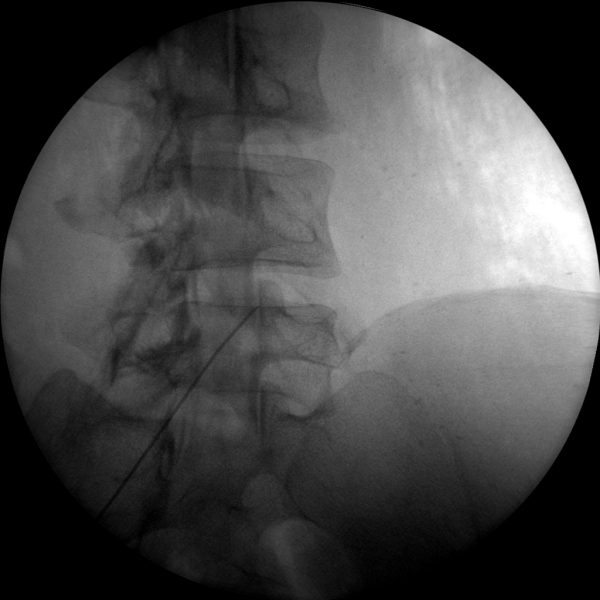

Skan-C is a highly versatile machine that can be used for a variety of pain management treatments, including epidural injections, nerve blocks, joint injections, and more.

Skan-C uses advanced imaging technology, such as pulsed fluoroscopy and digital subtraction angiography, to provide highly detailed images of the affected area. This allows doctors to perform procedures with increased precision and accuracy, and better patient outcome